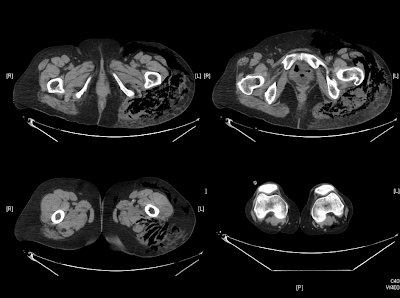

Entre

las 7h y las 10h, la paciente presenta progresivo empeoramiento clínico con

inestabilidad hemodinámica, hematuria, ictericia y crepitantes a palpación en

muslo izquierdo y Fosa iliaca izquierda. Se realiza nuevo control gasométrico arterial

aire ambiente (pH 7.39, pCO2 17.40, pO2 75.1, CO3H 10.4, Exceso base art -11.5,

láctico 14mmol, SatO2 95.4%), TC toraco-abd-pélvico urgente y se solicita

valoración por UCI decidiéndose traslado a dicha unidad.

- Fascitis/

Miositis nerotizante. Gangrena gaseosa - Se

- Ante

la sospecha clínica, siendo el cuadro típico dolor muy intenso, fiebre y

presencia de gas en tejido blando visto en pruebas de imagen (Rx, TC o RMN), es

necesario actuar de manera precoz mediante desbridamiento